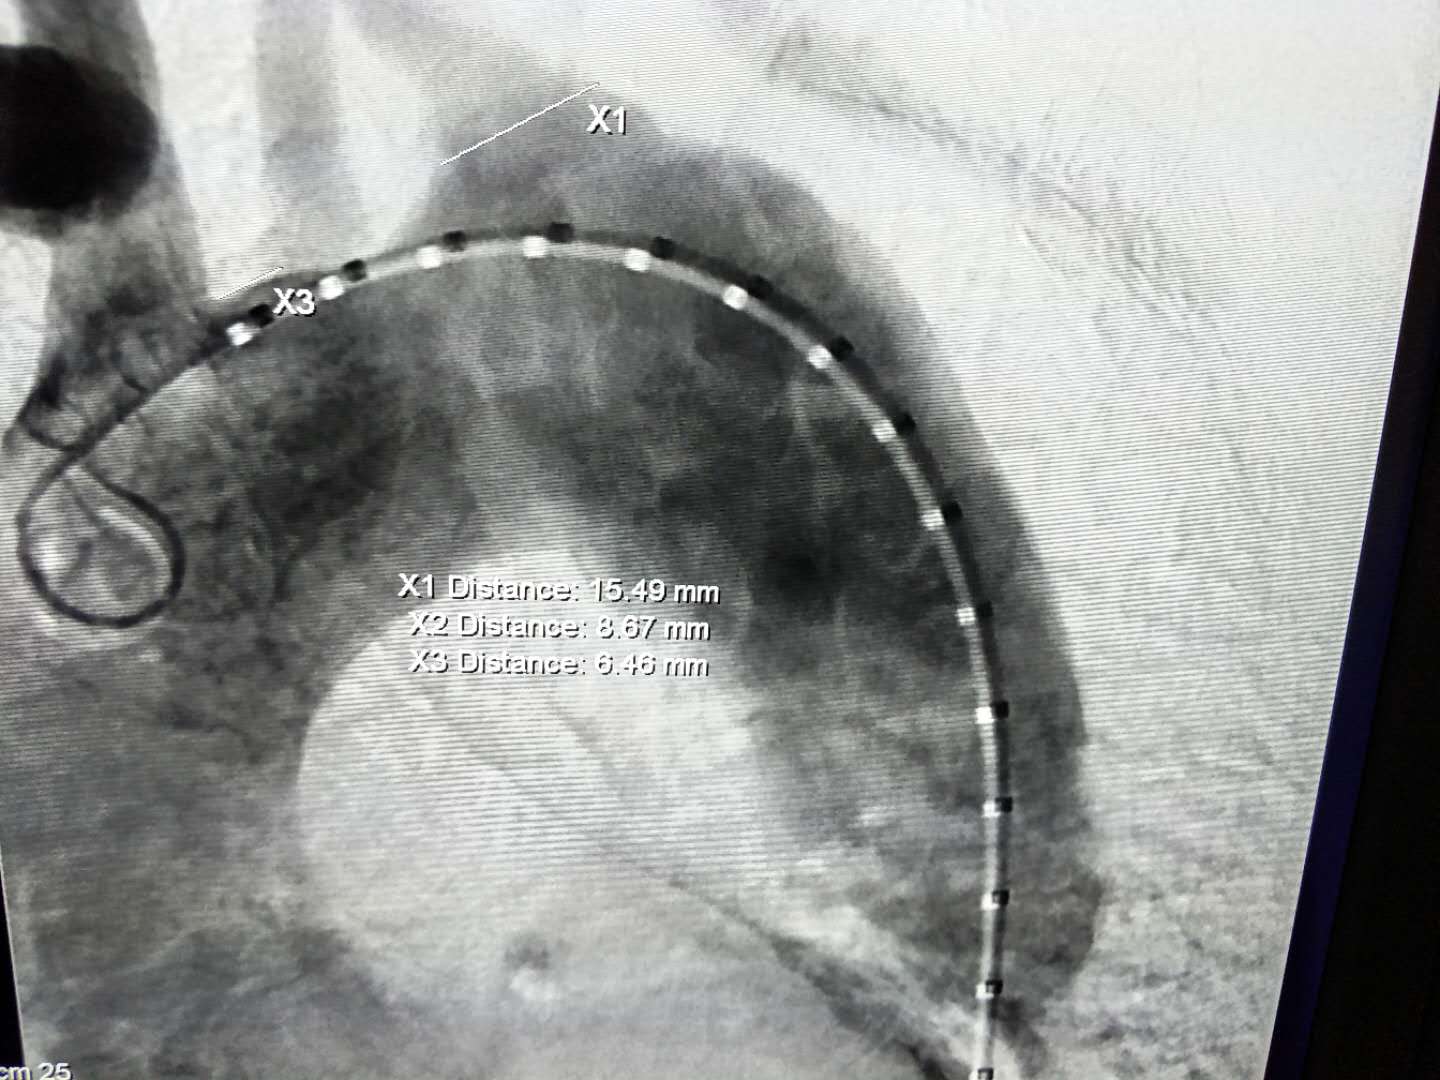

术中首先将体外开窗好的先健Ankura™ Pro主动脉主体覆膜支架输送到弓部,开窗位置对准颈总动脉后释放,然后从左肱动脉沿预置导丝送入裙边支架,精准定位后成功释放。最后,在左颈总动脉植入先健科技的Longuette™主动脉分支覆膜支架(裙边支架)保证开窗分支的血供。先健科技设计的裙边支架采用特殊的双层结构,其内层支架保证分支血管血液的通畅,外层裙边能有效封堵支架间的缝隙。术后造影显示,病变隔绝,分支血流通畅,裙边支架与主动脉支架贴合良好,术后效果良好。

(图:术后造影)